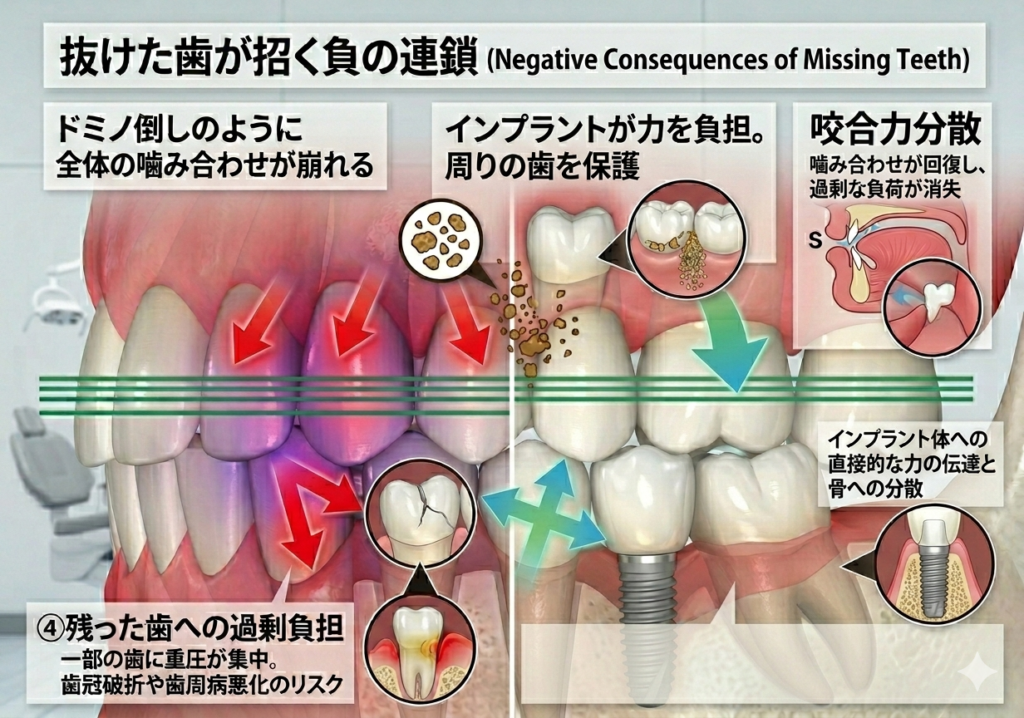

歯を失った後の「負のループ」を止める唯一の方法

これまでの治療(入れ歯・ブリッジ)と、インプラントには決定的な違いがあります。

これまでの治療:残った歯に「負担」をかける

インプラントがなかった時代、選択肢は「入れ歯」か「ブリッジ」の2つだけでした。

- 共通の弱点: 歯がない部分は「ダミー」なので、噛む力を支えられません。

- 結果: 残った数少ない歯が、抜けた歯の分のパワーまで肩代わりすることになります。

- 負の連鎖: 過剰な負担がかかった歯は、寿命が縮まり、破折(割れる)したり歯周病が悪化したりして、また次の歯が抜けてしまうという悪循環に陥りやすいのです。

インプラント:残った歯の「助け」になる

インプラントは、ただ見た目を補うだけではありません。

- 最大の特徴: 人工歯根が骨としっかり結合し、天然の歯と同じように「自分の力で噛み合わせを支える」ことができます。

- 結果: 他の歯に負担を押し付けないため、今ある健康な歯をこれ以上失わないよう守ることができます。